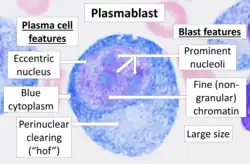

Multiple myeloma develops in B lymphocytes after they have left the part of the lymph node known as the germinal center. The normal cell type most closely associated with MM cells is generally taken to be either an activated memory B cell or the precursor to plasma cells, the plasmablast.[50]

The plasma cells seen in multiple myeloma have several possible morphologies. First, they could appear like a normal plasma cell, a large cell two or three times the size of a peripheral lymphocyte. Because they are actively producing antibodies, the Golgi apparatus typically produces a light-colored area adjacent to the nucleus, called a perinuclear halo. The single nucleus (with a single nucleolus with vesicular nuclear chromatin) is eccentric, displaced by an abundant cytoplasm. Other common morphologies seen, but which are not usual in normal plasma cells, include: